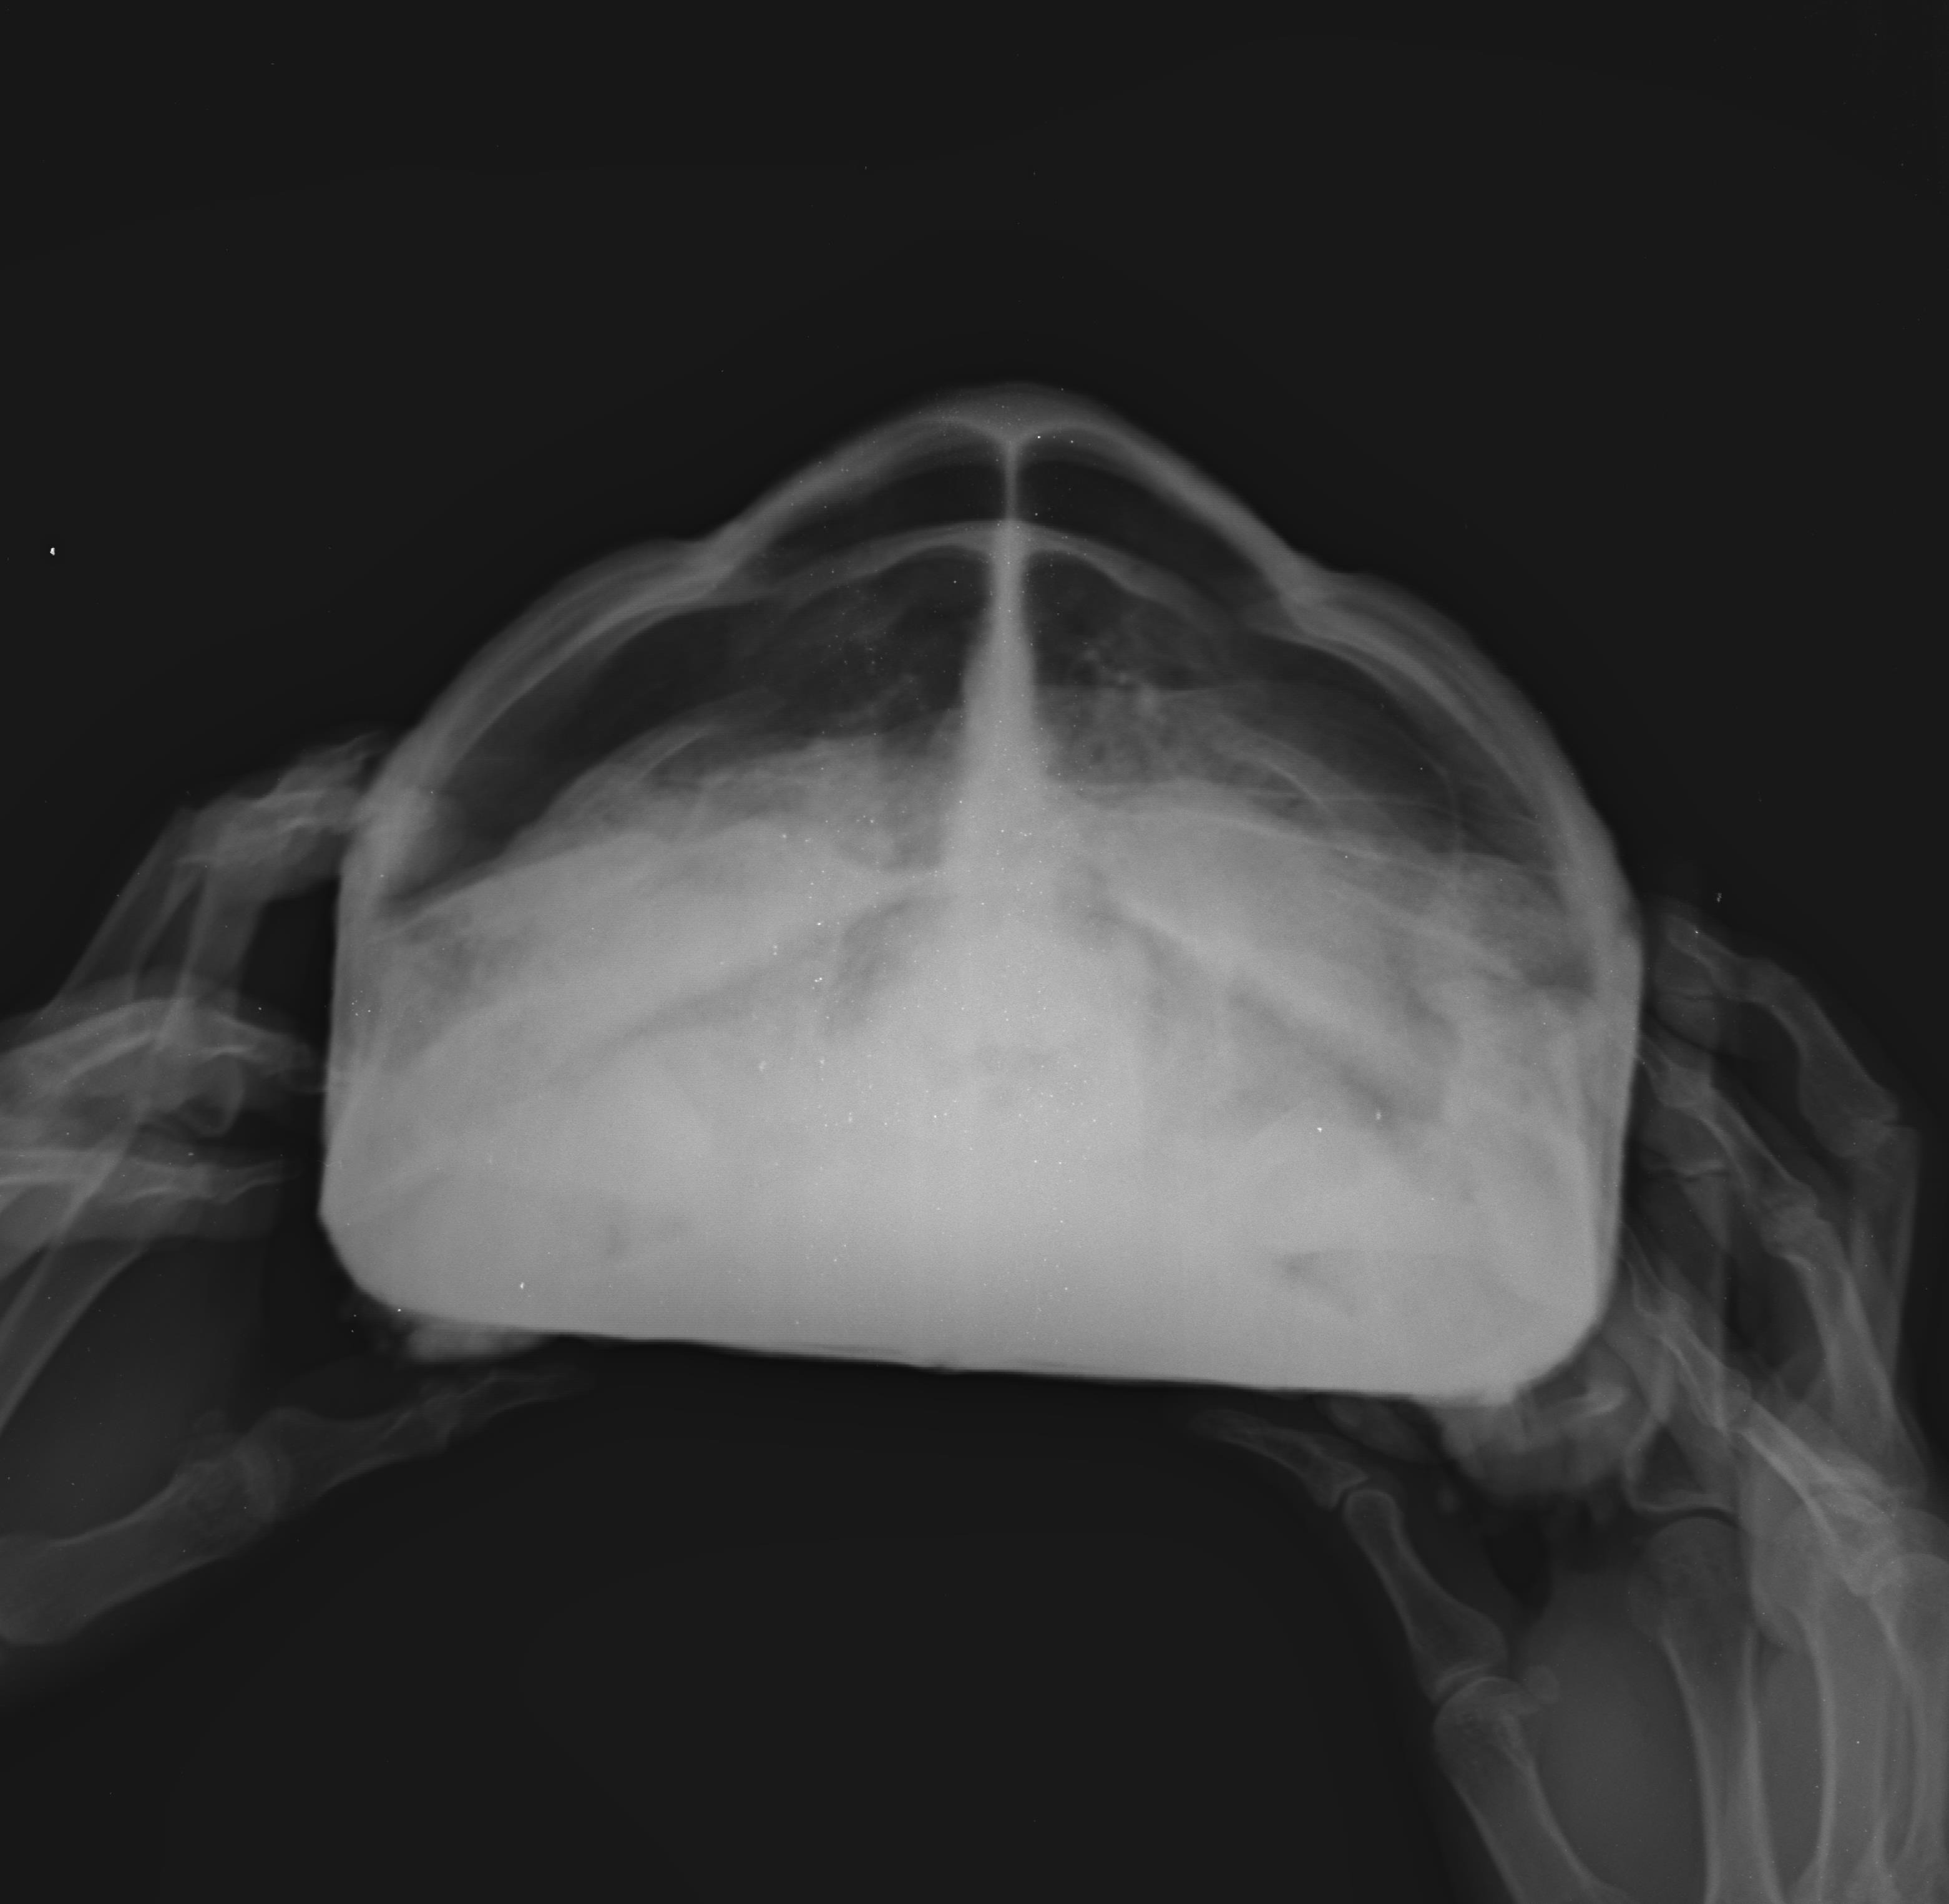

거북 X-Ray검사:정상(Normal)-레오파드거북 토르(11-08-2012, 2.6kg) 작성자가람캡틴|작성시간26.03.31|조회수2 목록 댓글 0 글자크기 작게가 글자크기 크게가 다음검색 현재 게시글 추가 기능 열기 북마크 공유하기 신고 센터로 신고 댓글 댓글 0 댓글쓰기 답글쓰기 댓글 리스트